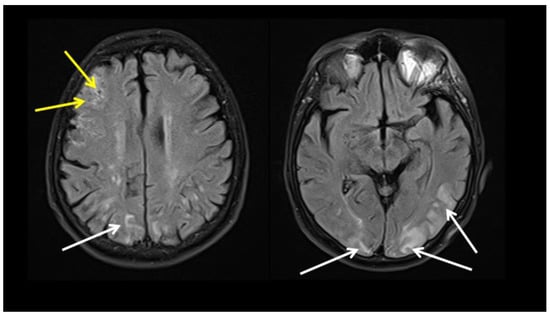

| Ivanovic J, et al., 2022 * [8] | 69 years, male | Headache, fever, elevated ESR, CRP, Fib, IL-6 | 6 weeks | LV-GCA Cerebral vasculitis | High dose CS, TPE Tocilizumab, IVIG, AZA | FDG PET CT Brain MRI | Improvement on treatment |